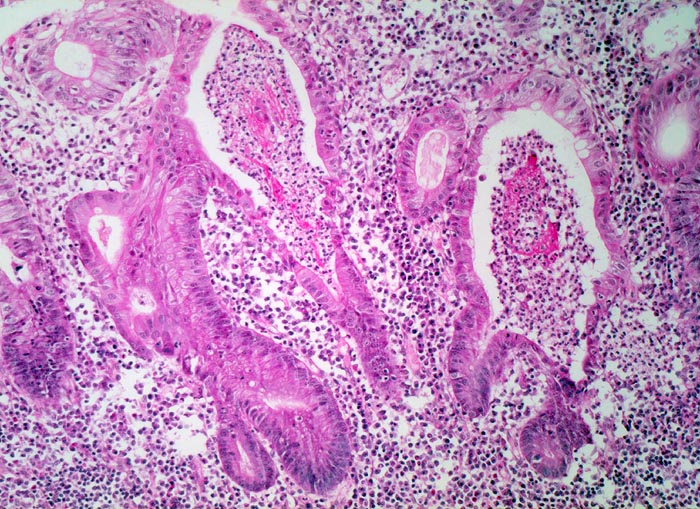

Die Colitis ulcerosa beginnt im Rektum (> 2758) und breitet sich kontinuierlich nach proximal aus. In 10% ist das gesamte Kolon (> 3364) befallen und es besteht zusätzlich eine back-wash-Ileitis im terminalen Ileum. Das Rektum ist bei unbehandelten Patienten praktisch immer befallen. Nach topischer Therapie kann das Rektum ausgespart sein und nach längerem Krankheistverlauf ist auch ein segmentaler Befall möglich. Bei fehlenden klinischen Angaben (Dauer der Erkrankung, Therapie) können diese atypischen Manifestationen diagnostische Schwierigkeiten verursachen. Makroskopisch finden sich häufig longitudinal ausgerichtete Ulzera mit Querverbindungen und Konfluenz. Residuelle Schleimhautinseln imponieren als Pseudopolypen. In der Remissionsphase ist die Schleimhaut glatt und blass, das Faltenrelief ist vergröbert und verstrichen und es finden sich häufig Granulationsgewebspolypen. Mikroskopisch findet sich je nach Entzündungsaktivität eine mehr oder weniger ausgeprägte diffuse Verdichtung des lymphoplasmazellulären Entzündungsinfiltrates mit Beimischung von Granulozyten in Form einer Kryptitis oder von Kryptenabszessen. Bei einer stark aktiven Entzündung finden sich zusätzlich Erosionen und Ulzera mit Ausdehnung der Entzündung über die Mukosa hinaus in die Submukosa oder in noch tiefere Schichten bei hochflorider Kolitis. Die Kryptenarchitektur ist gestört, die Anzahl der Krypten und der Becherzellen vermindert. In der Regeneratphase finden sich zahlenmässig reduzierte und verkürzte Krpyten mit normaler Anzahl Becherzellen. Meist bleibt eine leichte Verdichtung der Entzündungszellen in der Lamina propria bestehen.

Morphologische Merkmale:

• Abwechslungsweise oberflächliche Ulzera und pseudopolypöse Schleimhautvorwölbungen.

• Entzündungsinfiltrate in Mukosa und Submukosa.

• Unregelmässig geformte und verzweigte Krypten (Kryptenarchitekturstörung).

• Krpyten enden deutlich oberhalb der Lamina muscularis mucosae (Kryptenatrophie).

• Verminderte Schleimbildung und Becherzellverlust.

• Basal betonte Plasmozytose und Infiltrate neutrophiler Granulozyten.

• Ansammlungen neutrophiler Granulozyten in Kryptenlumina (=Kryptenabszesse) und Infiltrate von neutrophilen Granulozyten im Kryptenepithel (=Kryptitis).